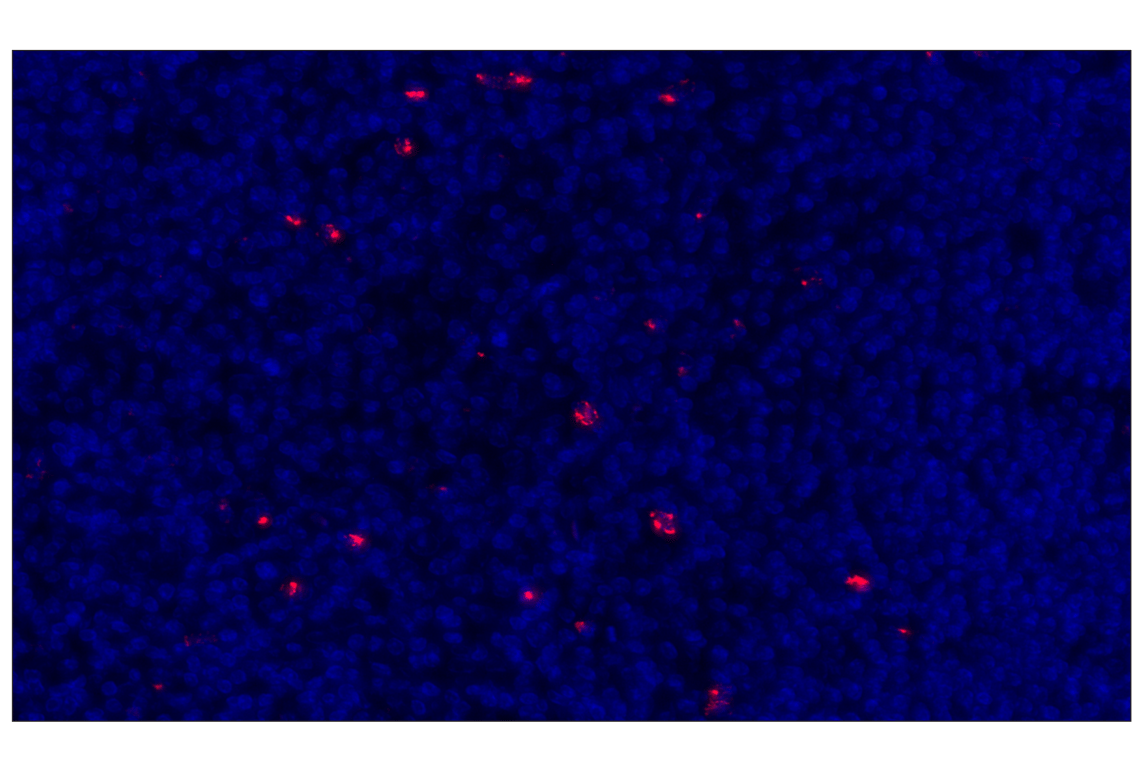

LAG3 (D2G4O) Rabbit Monoclonal Antibody (Alexa Fluor® 555 Conjugate) #56141

This Cell Signaling Technology® antibody is conjugated to Alexa Fluor® 555 fluorescent dye under optimal conditions. This antibody conjugate is expected to exhibit the same species cross-reactivity as the unconjugated LAG3 (D2G4O™) XP® Rabbit mAb #15372.

Immunohistochemistry (Paraffin) 1:100

LAG3 (D2G4O) Rabbit Monoclonal Antibody (Alexa Fluor® 555 Conjugate) recognizes endogenous levels of total LAG3 protein.